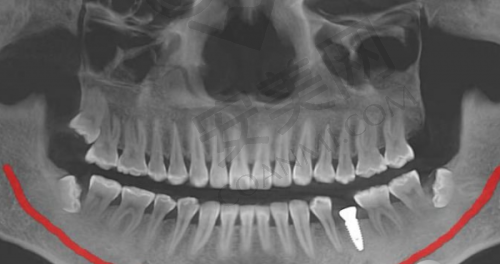

仅仅价格便宜可不行,种牙技术才是关键。汕头天佑口腔中 心在种牙技术方面有着坚实的保护。首先,它拥有一支专精的医疗团队。医生们不仅具备扎实的理论知识,还拥有丰富的临床实践经验。他们能够根据患者的具体情况,制定个性化的治疗方案,确保种植牙的成效和安心性。

其次,医院引进了精良的医疗设备。这些设备不仅能够提高种植牙的精细度,还能减少手术过程中的不适感,提升患者的体验。在手术过程中,医生可以借助精良的设备更正确地操作,大大提高了种植牙的成功几率。

再者,医院注重每一个细节,从术前检查、手术过程到术后护理,都有严格的医疗流程。术前会对患者进行全方面的检查,评估患者的口腔状况和身体状况,确保手术的安心性。手术过程中严格遵循规范操作,术后还会提供完善的护理服务,包括定期复查、口腔卫生指导等,确保种植牙的长期稳定和健康。